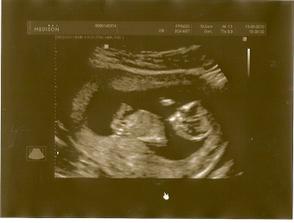

Pořídíme Míše Ríšu 🙂

tak se nám zadařilo počít sourozence, opět to byl fofr, první měsíc, takže opět trochu šok i když příjemný

zatím všechno vypadá krásně, mamince je dobře, doktoři jí hlídají na všech frontách, tak snad se nám tentokrát podaří dočkat se termínu 22.2.2011 🙂